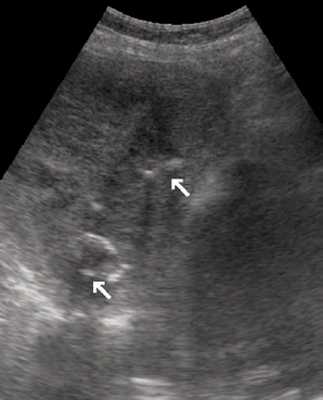

Женщина 50 лет, госпитализирована с болями в верхнем правом квадранте живота. Ультразвуковое исследование органов брюшной полости было проведено в день поступления (рис. 1а, б).

Рис. 1. УЗИ печени.

a) На эхограмме в правой доле печени видны два гиперэхогенных образования с четкими контурами (3,0x1,5 см, 2,5x1,5 см).

б) На эхограмме в левой доле печени видно большое гетерогенное образование (5.0x4.0 см), имеющее дольчатое строение.

Диагноз - множественная гемангиома печени